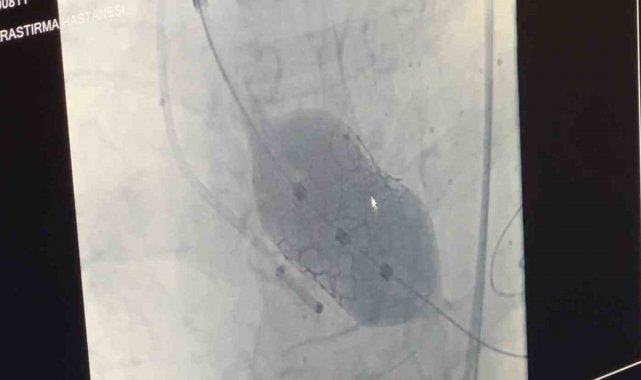

Samsun Eğitim ve Araştırma Hastanesi'nde 80 yaşındaki bir hastaya, nadir görülen dört yaprakçıklı aort kapağı nedeniyle transkateter aort kapak implantasyonu (TAVİ) yöntemiyle başarılı bir operasyon gerçekleştirildi. Operasyon, bu özelliği taşıyan vakalar arasında dünyada 18'inci, Türkiye'de ise ilk olma özelliği taşıyor.

Amasya'nın Merzifon ilçesinde yaşayan Muzaffer Uslu (80), göğüs sıkışması ve baygınlık şikayetleriyle başvurduğu Merzifon Devlet Hastanesi'nden Samsun Eğitim ve Araştırma Hastanesi'ne sevk edildi. Tetkikler sonucu, normalde üç yaprakçıklı olması gereken aort kapağının dört yaprakçıklı olduğu belirlendi. Samsun Üniversitesi Tıp Fakültesi Kardiyoloji Ana Bilim Dalı Öğretim Üyesi Doç. Dr. Mustafa Yenerçağ, kapak değişiminin açık ameliyatla yüksek risk taşıması nedeniyle kapalı yöntem olan TAVİ işlemiyle çözüm sağladıklarını söyledi.

Doç. Dr. Yenerçağ, işlem öncesi yapılan tetkiklerde karşılaştıkları nadir bulgu hakkında ise "Hastanın TAVİ işleminden önce yapılan tetkiklerinde aort kapağının 3 yaprakçıklı olması beklenirken çok daha nadir görülen 'Quadricuspid' adı verilen 4 yaprakçıklı aort kapağı saptadık. Daha önce böyle bir vaka ile karşılaşmamıştık. Literatürleri, akademik çalışmaları inceledik. 4 yaprakçıklı aort kapağının toplumda 100 bin kişide 4 görüldüğünü, taradığımız uluslararası yayınlarda ise 4 yaprakçıklı aort kapağı bulunan sadece 17 hastaya TAVİ işlemi yapıldığını saptadık. Ülkemizden bildirilen vaka örneği bulamadık. Diğer ülkelerde yapılan vakaları detaylıca inceledik. İleri tomografik analizleri yaptık. Vakamıza detaylıca hazırlandık" dedi.

"Doç. Dr. Serkan Sivri, asistan doktorlarımız Berkan Öztürk ve Enes Kaya ile Anestezi Uzmanı Aynur Kaynar hocamızla beraber ekip halinde hastamıza başarılı TAVİ işlemini yaklaşık 50 dakika içerisinde tamamladık. Hastamızı 1 gün yoğun bakımda takip ettikten sonra servis takibine aldık. Nadir görülen bu 4 yaprakçıklı aort kapağına yaptığımız TAVİ işleminin prosedürel detaylarını literatüre kazandırmayı planlıyoruz. Bizden sonra bu nadir vaka ile karşılaşan meslektaşlarımıza yol göstermesi açısından referans olacaktır."